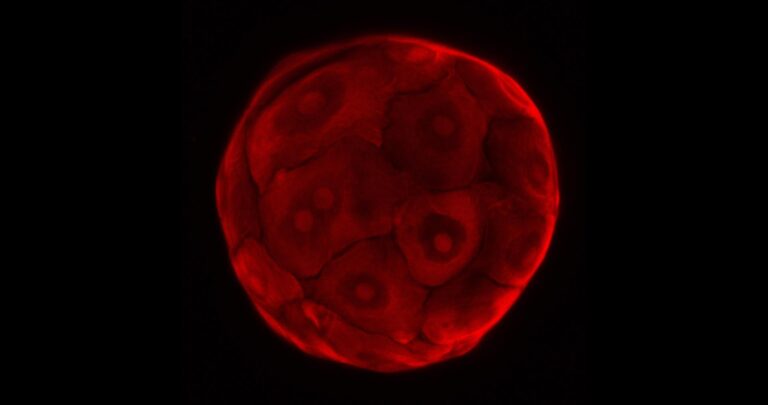

Tissues such as the intestine and liver typically take up and degrade pharmaceutically active compounds, or inactivate them. But before the efficacy of drugs can be tested in humans, scientists must assess whether they are safe for human consumption, which is largely determined by toxicity studies in lab animals such as mice and monkeys.Ethical issues aside, this is a somewhat flawed system as many drugs-in-development have proved safe in animals only to fail in human trials.Researchers associated with the TOXANOID project are evaluating whether a 3D-culture system that allows for the expansion of stem cells from the intestine and liver into so-called organoids – structures grown in a lab that largely mimic the functions of their respective tissues – can be used to reduce the dependence on animal-based toxicity studies.‘Any in-vitro assay (laboratory test) is always a reductionist assay … we’re looking at the intestines and the liver but the interconnections and interplay between organs is something that is very difficult to test in an in-vitro set up,’ said Dr Helmuth Gehart of the Hubrecht Institute in the Netherlands, who manages the activities of the TOXANOID project.‘Nevertheless, we strongly believe that by using these kind of assays in human cells, the need for testing in animals could be greatly reduced.’The TOXANOID project, which will be completed later this year, is an offshoot of a parallel project calledORGANOID, which developed this culture system. Currently, the researchers are testing whether their approach supersedes those currently used for in-vitro drug and chemical testing, namely cell lines and primary cells.ProliferateCell lines, which are laboratory-grown cultures of cells that are derived from one original cell, are advantageous because they can proliferate indefinitely in the right environment. However, they are derived from cancerous tissue and eventually do not resemble healthy tissue, leaving open questions of how well results will transfer.Primary cells, on the other hand, are cells taken directly from living tissue, but conversely are harder to acquire because they must come from healthy donors, which can be ethically questionable and expensive. Moreover, since these cells are short-lived, researchers also inevitably end up having to return to donors for more, leaving their sample subject to batch-to-batch variability.‘In principle we combine the best of both worlds in our organoid approach,’ said Dr Gehart, adding that if successful, their approach could reach industry partners in as quickly as two years.“’We strongly believe that by using these kind of assays in human cells, the need for testing in animals could be greatly reduced.’Dr Helmuth Gehart, Hubrecht Institute, NetherlandsAnother approach to bypass the use of animal testing – which has been banned in the EU cosmetic industry since 2013 – is the use of human induced pluripotent stem cells (hiPSCs) for toxicity testing. This technology, pioneered in a Japanese lab in 2006, allows for mature human cells to be reprogrammed such that they can self-renew indefinitely and give rise to every other cell type in the body, a competence previously limited to embryonic cells.The in3 project aims to differentiate hiPSCs from the same genetic background into tissues including the brain, lung, liver and kidney, and expose them to several chemical compounds. The data generated will be used to develop safety assessment approaches by integrating biological and computational methods.‘Once the induced pluripotent cells have been generated we can expand the cell numbers, thus creating a virtually unlimited source of the donor’s cells with their unique genetic code,’ said Professor Paul Jennings, coordinator of in3. ‘These cells can then be differentiated into different cell and tissue types.’PredictionThe proof-of-concept study, which will be completed by 2020, is focused on developing testable prediction models, by incorporating information about how the test chemical likely gets around the body and is absorbed and eliminated, which tissues are more involved in its toxicity and which biological pathways are disturbed or activated upon exposure.Then, computational techniques can be used to ‘link all the data from the different tissues into a virtual human subject,’ said Prof. Jennings, who also leads the molecular and computational toxicology division at the chemical and pharmaceutical department of VU Amsterdam in the Netherlands.Prof. Jennings cautioned the project was fairly early in the scientific process.Adoption of non-animal methods in any industry will depend on whether there’s an uptake by regulators, he says.‘I think the science is catching up quickly, but we still need to do a better job in interacting with our regulatory colleagues.’The research in this article was funded by the EU. If you liked this article, please consider sharing it on social media.The IssueIt is already illegal for companies to sell cosmetic products such as make-up, shampoo and soaps that have been tested on animals. Now the challenge is to create alternative testing approaches for other products such as pharmaceuticals and chemicals.The EU is working with companies to help replace, reduce and refine animal use in regulatory testing, an approach known as the 3Rs. TheEuropean Partnership for Alternative Approaches to Animal Testingis a collaboration between the EU, trade associations and companies from seven industry sectors, to develop alternatives approaches.The EU’s in-house research service, theJoint Research Centre, is also helping to develop new safety prediction models for chemicals by combining lab-based tests with computational modelling.